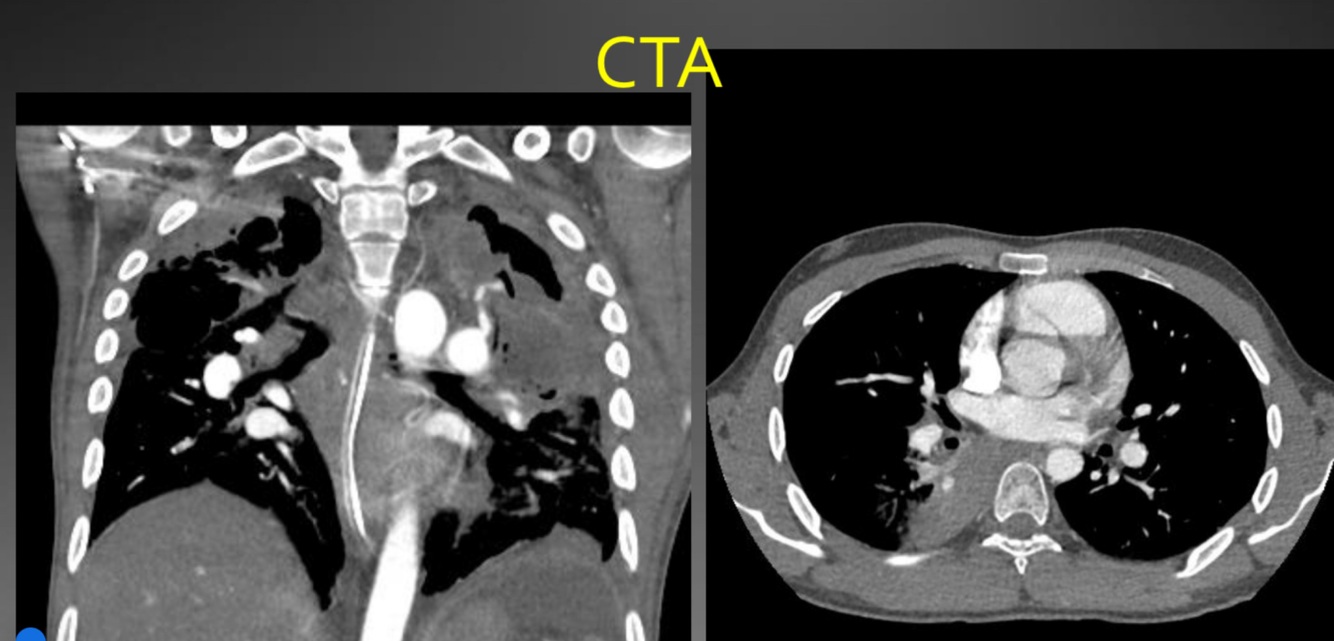

Complications post tb

Haemoptysis do CTA

BA hypertrophy & Rasmussen’s pseudoaneurysm